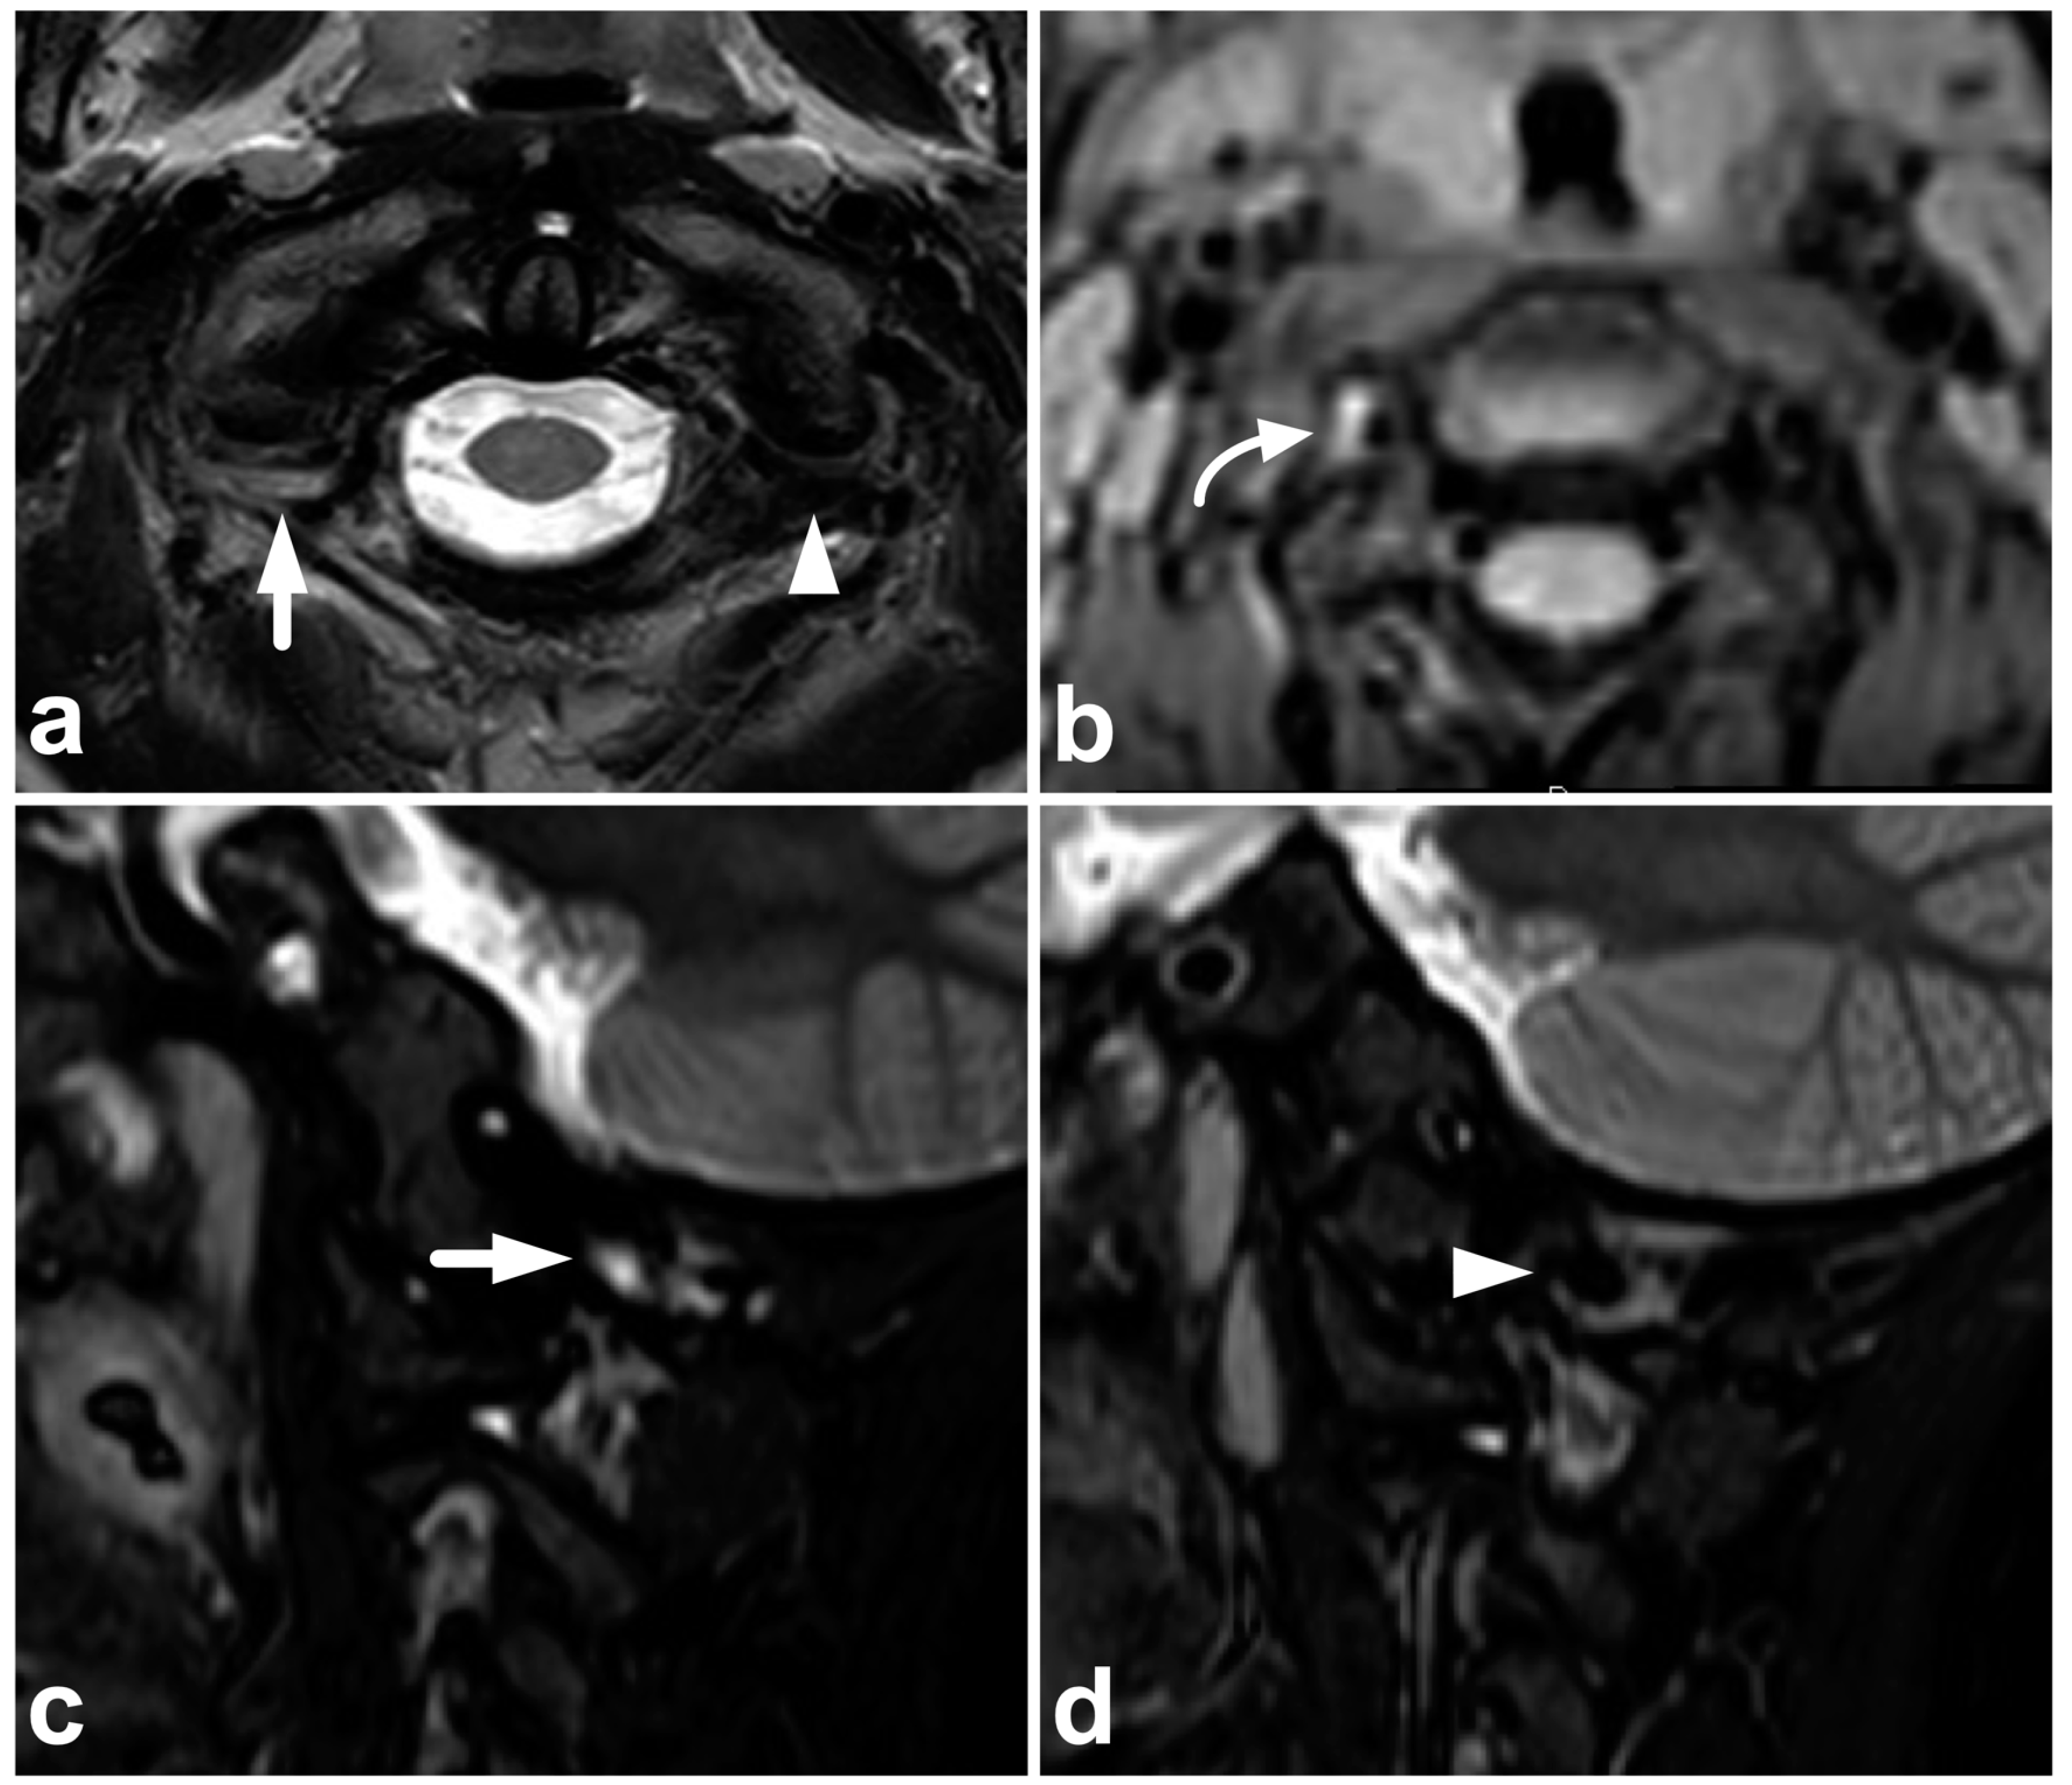

Figure 21.

(a) NECT, coronal reconstruction with a bone kernel. (b) NECT, sagittal reconstruction with a bone kernel. (c) Sagittal STIR. (d) Coronal STIR. A 9-year-old male, neck pain and midline cervical tenderness after diving into shallow water. Small osseous fragments were seen at the anteroinferior corners of vertebral bodies C5 and C6 (arrows). The imaging appearance was consistent with inferior ring apophyses, but due to cervical spine symptoms and high-risk injury mechanism, MRI was performed. STIR imaging did not show any edema, neither in the proximity of the ring apophyses nor elsewhere in the spine. The apophyses were not visible at MRI.